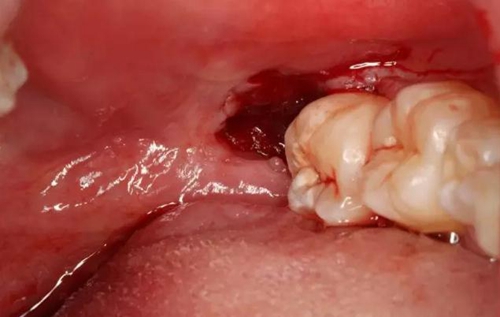

圖8.半小時后、拔牙創(chuàng)出血停止、無需縫合

圖9.拔除的38牙齒